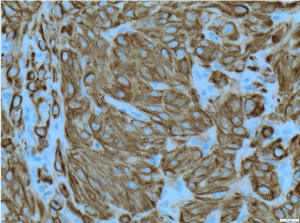

Histological features and immunoprofile of metastatic high grade sarcomatous renal carcinoma of left supraclavicular lymph node were depicted in Figures 4-11.

Figure 7. CK8/18 X200 immunohistochemistry-Tumour cells are positive for cytokeratin [CK] 8/18 X200

Figure 8. EMA X200 immunohistochemistry-Tumour cells are positive for epithelial membrane antigen [EMA] X200